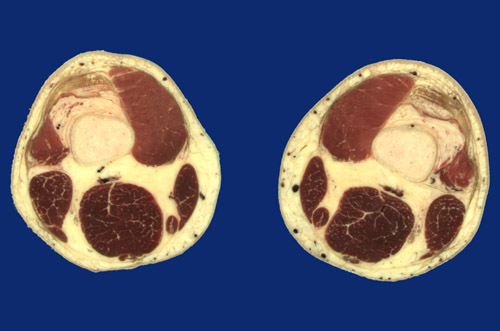

Identify the following regions in the image above: Great saphenous vein - Popliteal vessels - Vastus medialis - Vastus lateralis - Sartorius - Gracilis - Semitendinosus tendon - Semimembranosus - Biceps femoris - Suprapatellar synovial bursa - Articularis genus - Quadriceps tendon - Femur